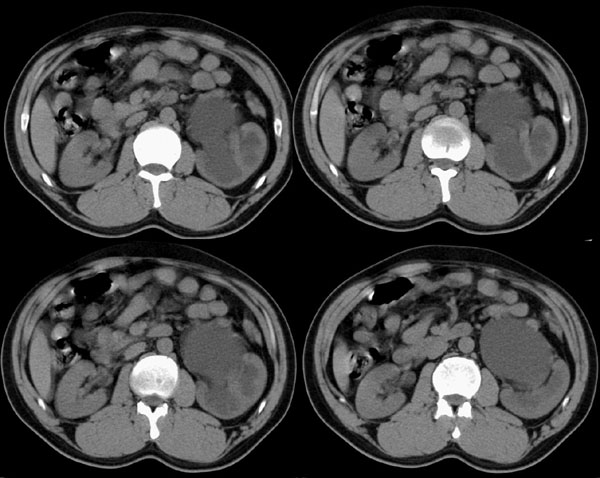

左输尿管上端狭窄(先天性,或血管压迫所致)伴肾积水.

左侧肾盂、肾盏扩张,肾盂输尿管移行部突然狭窄,未见明显占位及高密度结石影,体检发现,考虑:先天性肾盂输尿管移行部狭窄。(原因多方面,有先天缺陷造成移行部结构异常或因为迷走血管、纤维索条引起肾盂输尿管的压迫扭曲所致。)大剂量ivp或肾盂造影有助于显示输尿管狭窄部位及形态。

支持!建议逆行造影或穿刺顺行造影进一步检查。